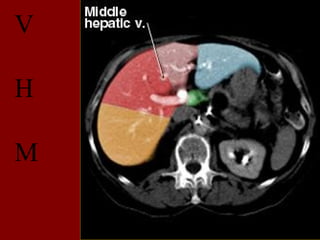

V

H

M

e

D

INCISÃO SOBRA AVEIA HEPÁTICA DIREITA

INCISÃO SOBRE AVEIA HEPÁTICA MÉDIA.

INCISÃO SOBRE AVEIA HEPÁTICA ESQUERDA.